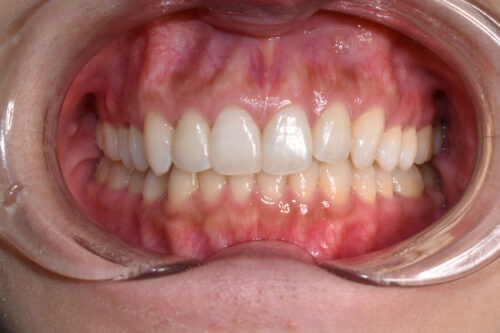

歯のがたつき(叢生)と過蓋咬合を非抜歯矯正治療で治した症例(かみ合わせ変化10か月)

初診時年齢 27歳 女性

歯のでこぼこ(叢生)

と

過蓋咬合

を主訴に

右側が アングル2級とよばれる

出っ歯傾向の状態で

上の正中が

半歯分 ずれている状態でした。

また 下あごの 歯が見えず

過蓋咬合を呈していました。

ワイヤー矯正治療10か月後です。

本症例も

上顎左右臼歯部に

歯科矯正用アンカースクリュー(デュアル・トップオートスクリュー)を用い

下あごを オートローテーションさせ

また 上下の歯列全体を

後方へ移動させることで

歯を抜かなくても

口元の改善も行いました。

上下の正中には 若干ずれが残存しましたが、

かみ合わせ重視で

終了いたしました。